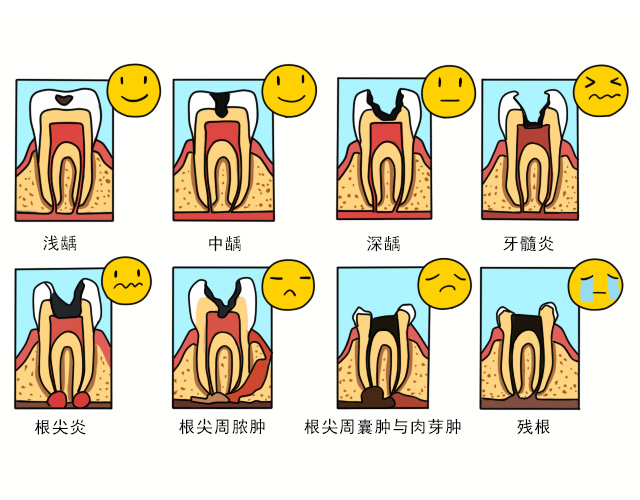

牙齿病变史插漫类科普